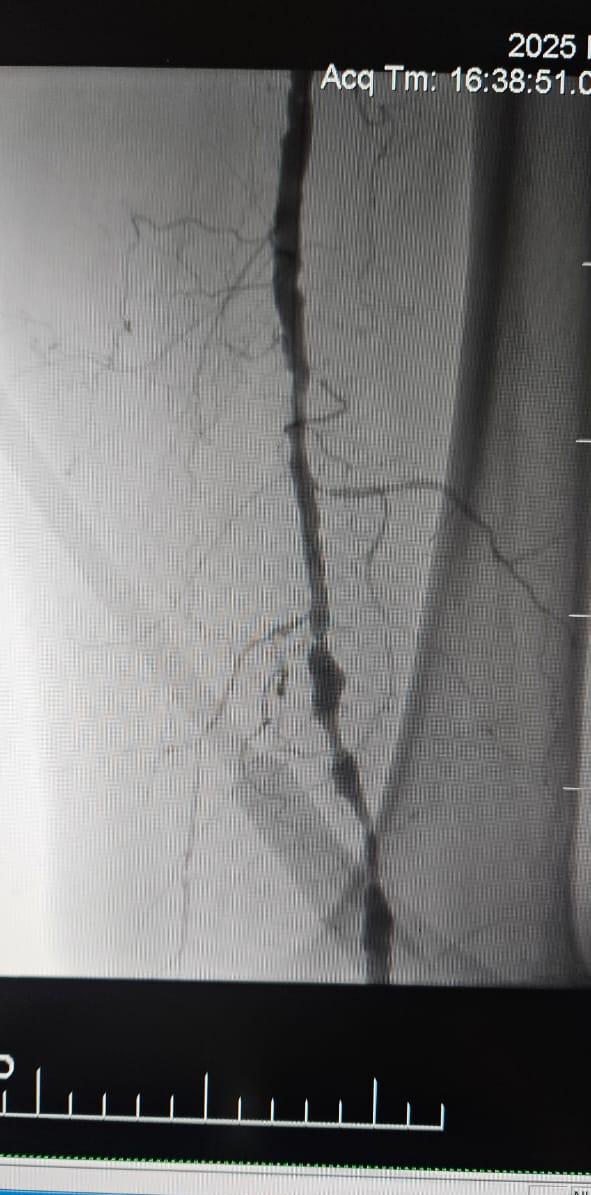

We are pleased to share a successful case from a hospital in Batumi, Georgia, where a 78-year-old female patient with Critical Limb Ischemia (CLI) caused by chronic total occlusion of the lower limb artery showed remarkable clinical improvement following treatment with the ThorCrack Peripheral IVL Balloon Dilatation Catheter System.

This case underscores the clinical value of intravascular lithotripsy (IVL) in the treatment of complex CLI cases with long-segment chronic occlusion—particularly in patients with heavy calcification, where traditional balloons or atherectomy devices may have limited efficacy.